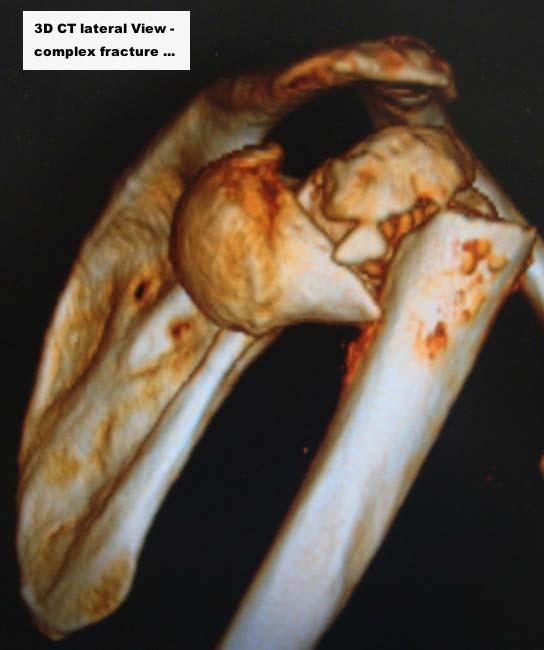

Here are some photos, of chronic, locked, 4 part posterior dislocation, 2 months old, that I did September/2011. Patient is 67, very, very active - had a really reasonable, honest clinical result ...

Photos attached ...